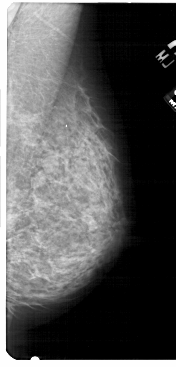

A_1755_1.LEFT_CC

LEFT_CC LINES 5236 PIXELS_PER_LINE 2506 BITS_PER_PIXEL 12 RESOLUTION 43.5 OVERLAY